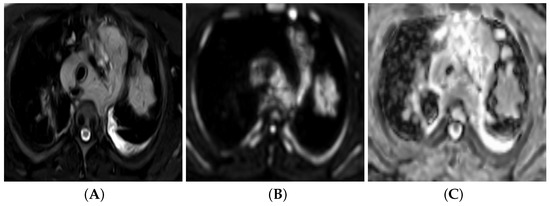

PET/MRI

3.6. Diffusion-Weighted Imaging (DWI)

3.6.1. DW Imaging Protocol

3.6.2. Qualitative Image Analysis

3.6.3. Quantitative Image Analysis